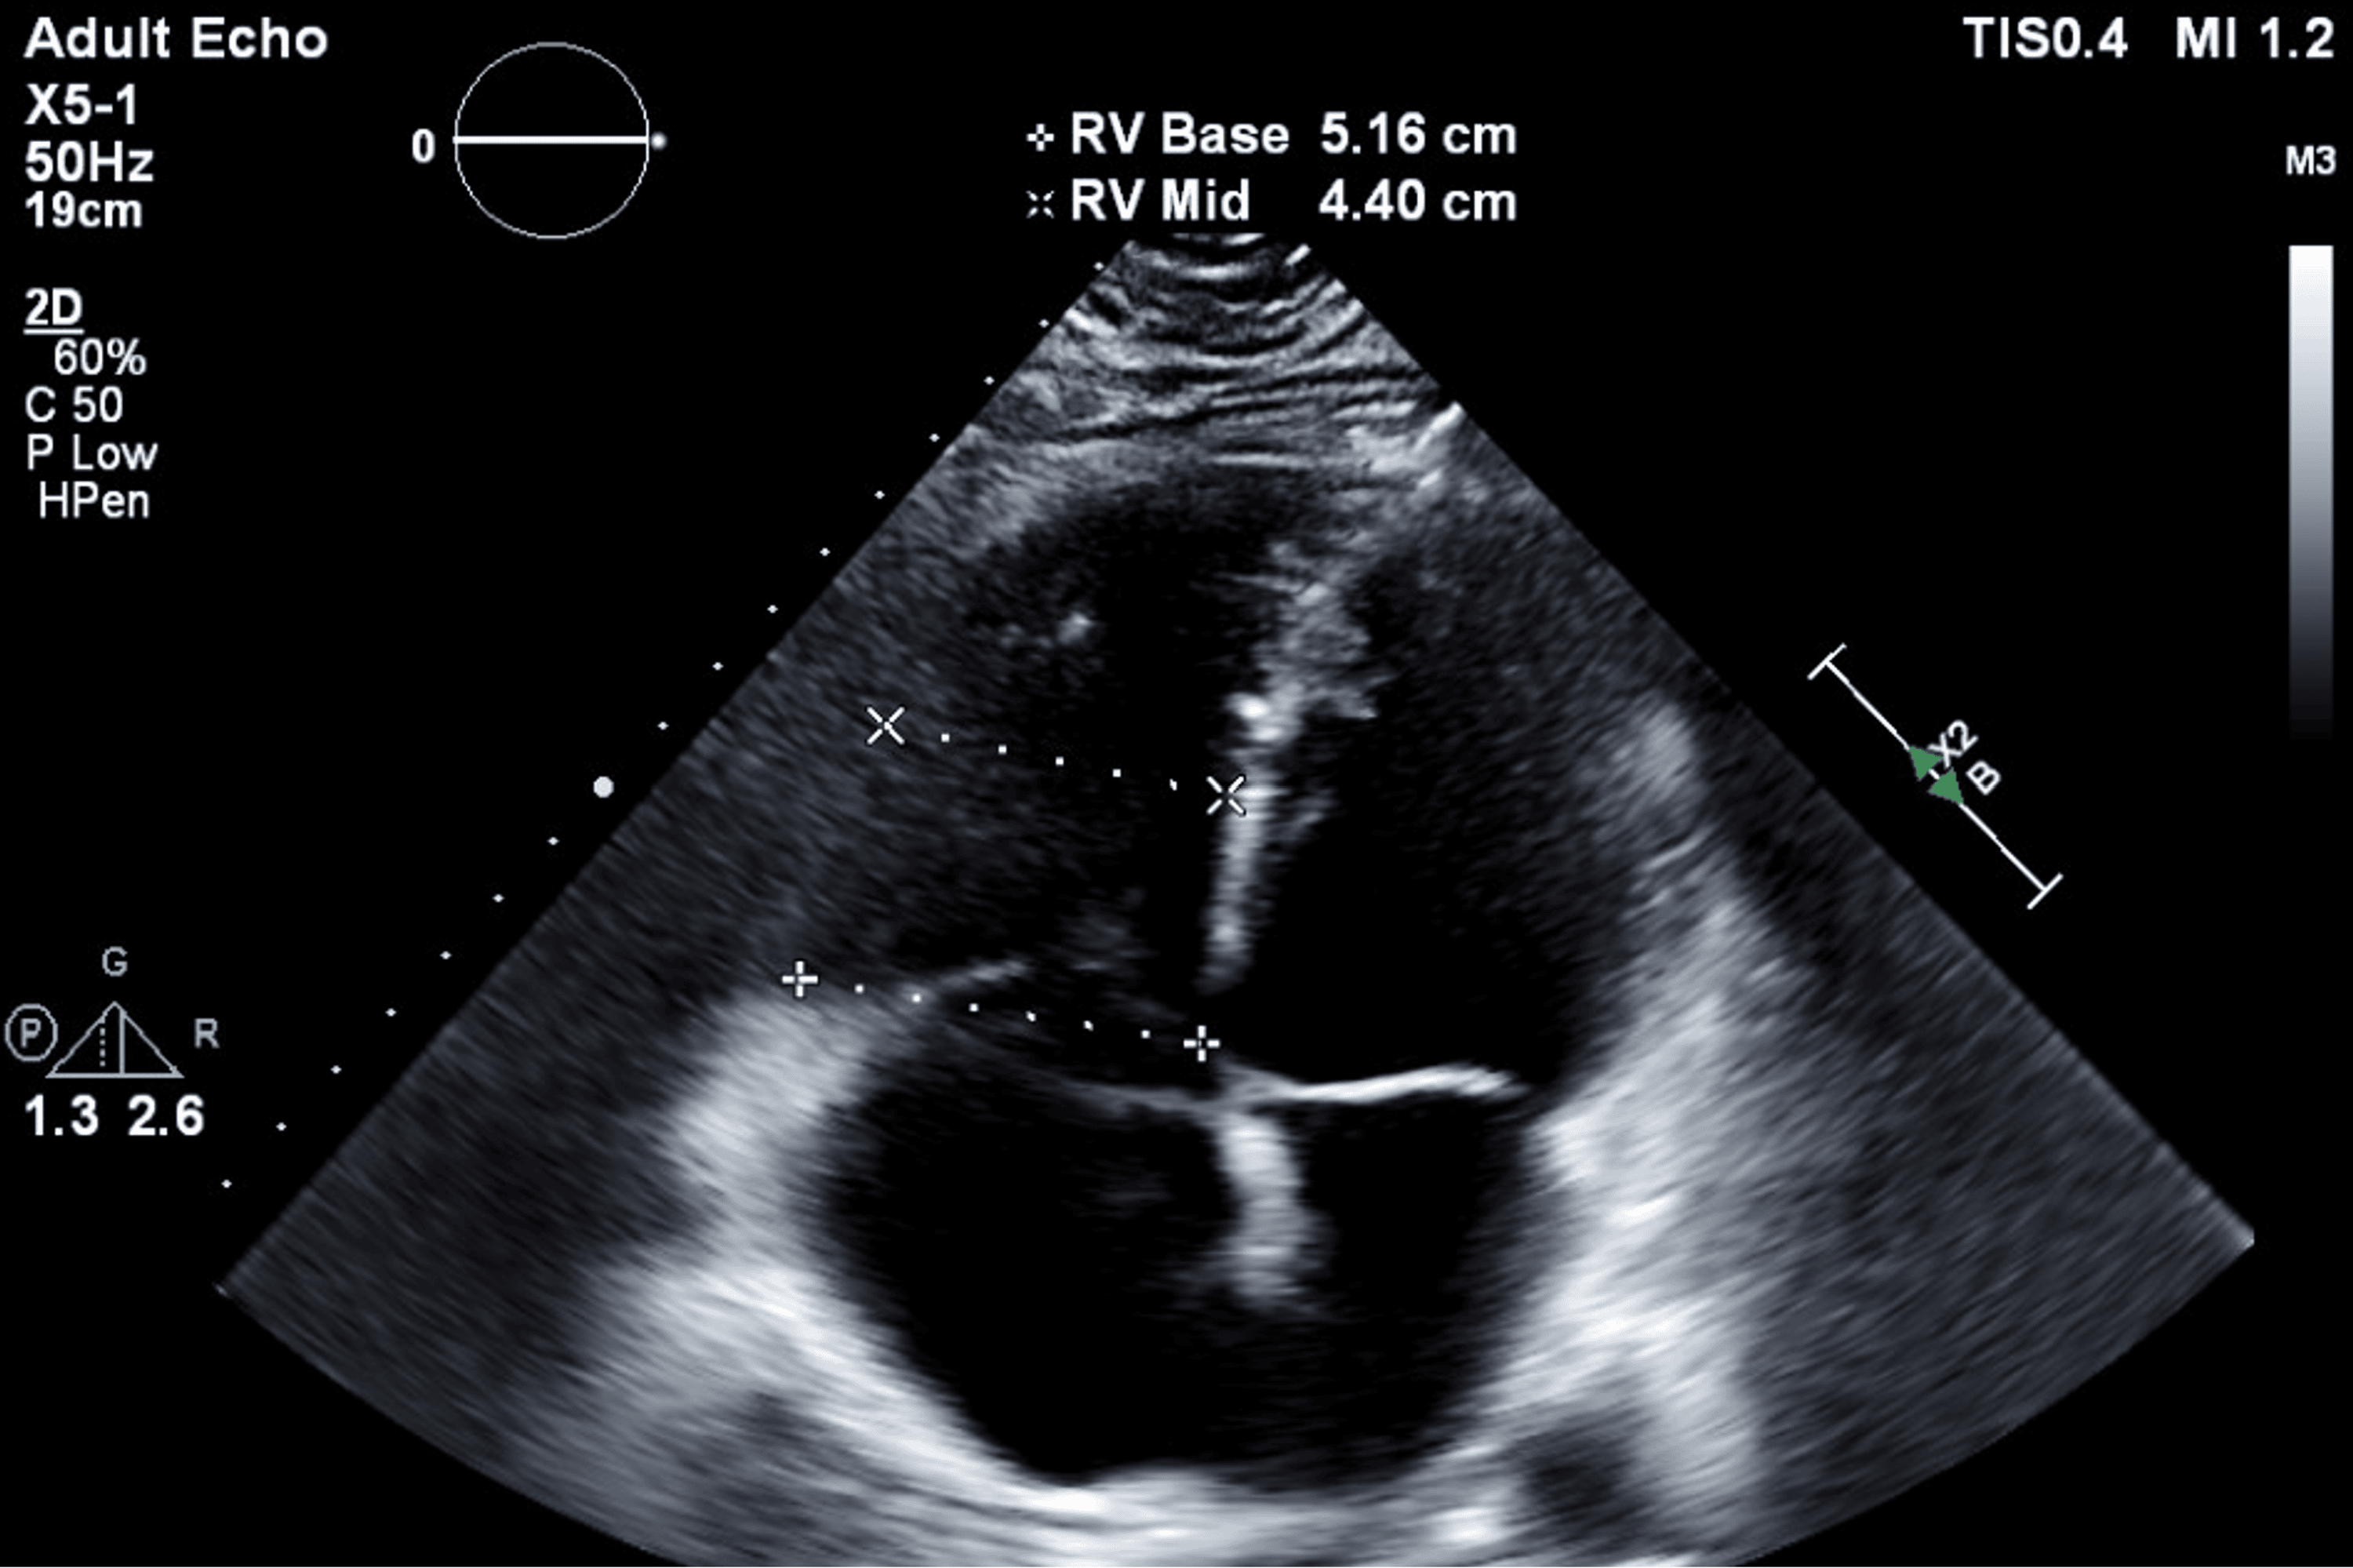

From www.cureus.com

Persistent Peril Recurrent Deep Vein Thrombosis and Pulmonary Embolism Protein S Deficiency Pulmonary Embolism Protein s deficiency is an inherited thrombophilia associated with an increased risk of thromboembolism. Conditions such as protein s deficiency, resulting from genetic mutations, are encompassed within this category of causative. Free and total protein s deficiency was not associated with venous. Having this deficiency puts you at risk for a blood clot in your leg or arm veins that’s. Protein S Deficiency Pulmonary Embolism.

Persistent Peril Recurrent Deep Vein Thrombosis and Pulmonary Embolism Protein S Deficiency Pulmonary Embolism Subjects were regarded protein s deficient when protein s levels were <2.5th percentile of the controls. Conditions such as protein s deficiency, resulting from genetic mutations, are encompassed within this category of causative. Having this deficiency puts you at risk for a blood clot in your leg or arm veins that’s known as a deep vein thrombosis (dvt). Free and. Protein S Deficiency Pulmonary Embolism.

Persistent Peril Recurrent Deep Vein Thrombosis and Pulmonary Embolism Protein S Deficiency Pulmonary Embolism Subjects were regarded protein s deficient when protein s levels were <2.5th percentile of the controls. There are several genetic conditions known to increase the risk of vte including factor v leiden, prothrombin gene mutation (g20210. Having this deficiency puts you at risk for a blood clot in your leg or arm veins that’s known as a deep vein thrombosis. Protein S Deficiency Pulmonary Embolism.

Persistent Peril Recurrent Deep Vein Thrombosis and Pulmonary Embolism Protein S Deficiency Pulmonary Embolism There are several genetic conditions known to increase the risk of vte including factor v leiden, prothrombin gene mutation (g20210. Conditions such as protein s deficiency, resulting from genetic mutations, are encompassed within this category of causative. Subjects were regarded protein s deficient when protein s levels were <2.5th percentile of the controls. Protein s deficiency is an inherited thrombophilia. Protein S Deficiency Pulmonary Embolism.